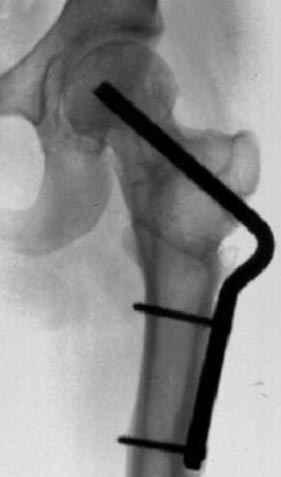

Отправитель: Alexander Chelnokov 23 Ноябрь 2004, 02:31

Если, например, доводится лечить больных с псевдартрозами шейки бедра, то надобность есть, и приходится. См. приложение.

Несколько снимков из моей коллекции, чтобы разьяснить, почему мы до сих пор делаем различные варианты остеотомии.

На рисунке N1 предоперационный план лечения ложного сустава шейки бедра- линия ложного сустава, угол и направление введения импланта, клиновидная остеотомия в градусах и миллиметрах, второй снимок после коррекции, расчет, на сколько удлиняется конечность и размеры импланта;

N3 рисунок окончательный снимок, после операции моя рентгенограмма должен выглядеть примерно как эта картина. На N4 снимке клин перед удалением; N5 послеоперации 3 нед.; N6 окончательная рентгенограмма.

варус при проксимальном отделе 95 градусной пластиной.